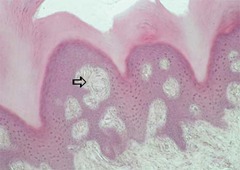

Meissner's corpuscles

Front

sensitive touch receptors in the dermis